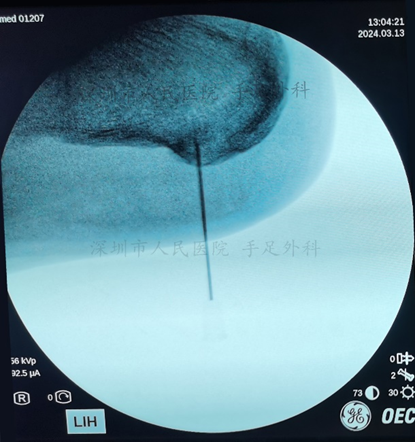

图7:术中证实跟骨骨刺已清除

图7:术中用磨钻磨除跟骨骨刺,清理骨刺周围的炎性组织。